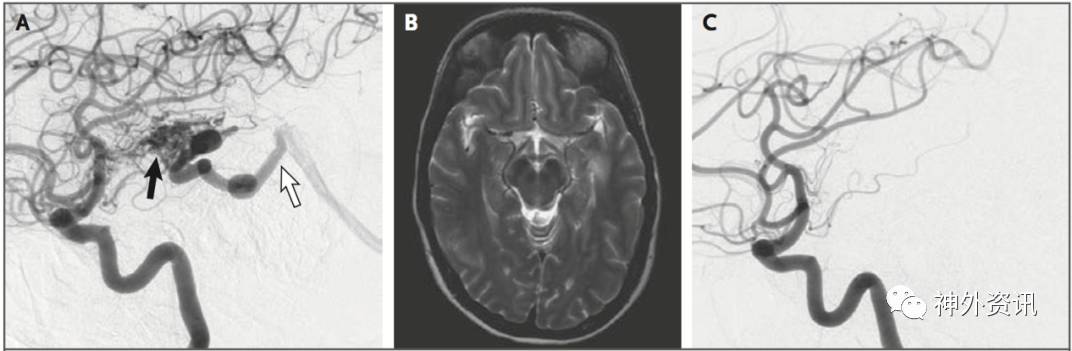

图1. 52岁女性患者,3级AVM,因左侧脑室颞角少量出血入院。A. DSA示最大径1.8cm AVM病灶(黑箭头),由左侧大脑中动脉的分支豆纹动脉供血,由深静脉引流至Galen静脉(白箭头);B.患者伽玛刀18Gy边缘剂量治疗3年后的MRI-T2轴位加权像显示,未见残存流空影;C.伽玛刀治疗3年后DSA复查示,AVM消失。

立体定向放射外科是一种已经充分研究的AVM治疗方式,包括伽马刀、射波刀和质子束等,可以使畸形血管逐渐硬化和病灶闭塞。AVM是否成功闭塞取决于病灶大小和病灶边缘的放射剂量(边缘剂量)。通常,畸形血管团越小,立体定向放疗效果越好;VRAS分级1级或2级的畸形血管团(<4cm3)给予18Gy或以上剂量治疗后,通过MRI成像和DSA复查显示,病灶闭塞率可以达到80%;较大的3级、4级或5级病灶,给予较低的边缘辐射剂量治疗,在相同时间内,病灶闭塞率不足一半,占48%,但相关的放射性坏死风险较高,占3%(图1)。立体定向外科起效时间较慢,平均约需2-4年;而伽玛刀治疗后的2-4年出血风险较治疗前仅轻微降低。一项含2236例AVM患者的随访报告显示,立体定向放射外科治疗后的年出血率为1%;完全闭塞并无任何并发症患者,在Spetzler-Martin分级法1级或2级AVM中为70%、3级AVM中为56%和4级AVM中为35%。鉴于4级或5级AVM放射治疗反应差,可以采用分期、聚集方法放疗。